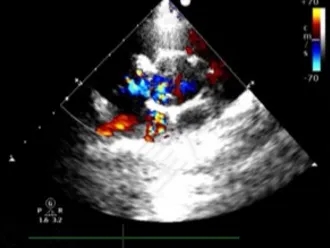

牵拉成型线锁定后,分流消失,主动脉瓣反流消失。

封堵器锁定后呈“蝴蝶状”明显盘状形态,室水平分流完全消失,主动脉瓣反流消失。

牵拉试验,封堵器稳定无移位,释放封堵器后超声下确认无残余分流,无主动脉瓣反流,三尖瓣反流同术前无增加。

大动脉短轴切面,封堵器释放后双盘紧贴间隔,呈现完美“工字形蝴蝶形”,顺应VSD形态及瓣膜形态。

MemoSorb全降解VSD封堵器展现了极佳的顺应性,在通过长隧道、小出口的VSD后,能顺利从“长哑铃”形态展开并固定为贴壁良好的“蝴蝶”形态。术后即刻超声评估显示,伞盘封堵完全,对相邻瓣膜无任何影响,主动脉瓣及三尖瓣均未出现反流。